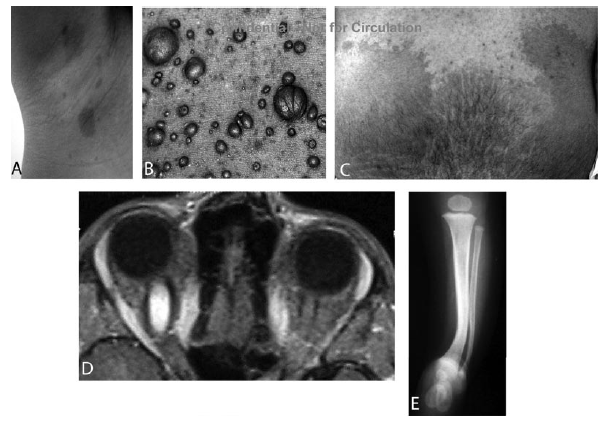

Sebbene esse possano essere presenti alla nascita, usualmente si sviluppano dai primi mesi di vita ai due anni di et�. La loro comparsa � spesso il primo aspetto delle NF1 (Figura 1). Il numero delle macchie pu� essere elevato, fino a molte dozzine, ma n� il loro numero n� la loro grandezza sono legati alla gravit� della malattia. La grandezza e il numero di queste macchie � invece importante per la diagnosi: la presenza di ≥ 6 macchie caff� e latte di > 0,5 cm di diametro prima della pubert� o di 1,5 cm di diametro dopo la pubert� � il primo criterio diagnostico (Figura 2). Le macchie caff� e latte non hanno tendenza a una trasformazione maligna. Per i pazienti che sono disturbati dalla loro presenza, � possibile dare dei consigli su come camuffarle. D'altra parte non ci sono prove a favore delle terapia laser per la loro rimozione.

Figura 2. Aspetti clinici della neurofibromatosi.

Le efelidi alle ascelle e all'inguine (segno di Crowe) si riscontrano pi� speso a 3-5 anni di et�. Queste efelidi sono tipicamente piccole (2-3 mm di diametro), iperpigmentate.

Altre sedi delle efelidi sono: l'area fra le palpebre, intorno al collo, sotto il seno. In alcuni pazienti le efelidi possono essere presenti al di l� di queste regioni.

I noduli di Lisch sono degli amartomi melanocitici dell'iride che non disturbano la visione (Figura 3). Essi tipicamente compaiono fra i 5 e i 10 anni di et�: si rendono ben visibili a un oculista con esperienza mediante una lampada a fessura. I noduli di Lisch sono patognomonici della NF1 e debbono essere distinti dai nevi dell'iride, che si osservano nella popolazione in generale.

Figura 3. Neurofibromatosi 1. Amartomi pigmentati dell'iride (noduli di Lisch) (Zitelli BJ et al, 2002)

La displasia delle ossa lunghe, come la displasia tibiale congenita con pseudoartrosi, porta a un'incurvatura della gamba. L'osso presenta un assottigliamento della corticale, che predispone a fratture patologiche per il carico del peso nel primo anno di vita. Le ripetute fratture e l'incapacit� a guarire determina la pseudoartrosi. La pseudoartrosi risponde poco alla chirurgia per la grave osteopenia, per cui alcuni pazienti vanno sottoposti ad amputazione. Un trattamento precoce con bifosfonati pu� risultare utile.